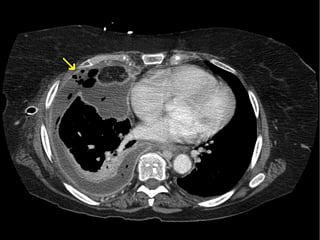

TAC abdominal

• En lesiones tardias puede detectar los biliomas,

abscesos hepáticos o atrofia/ hipertrofia hepática

• El principal valor de la TAC es identificar el lugar de

la obstrucción

Diagnóstico

Pande H. L: bile duct. E medicine Journal. 2002,3 : 1-30.